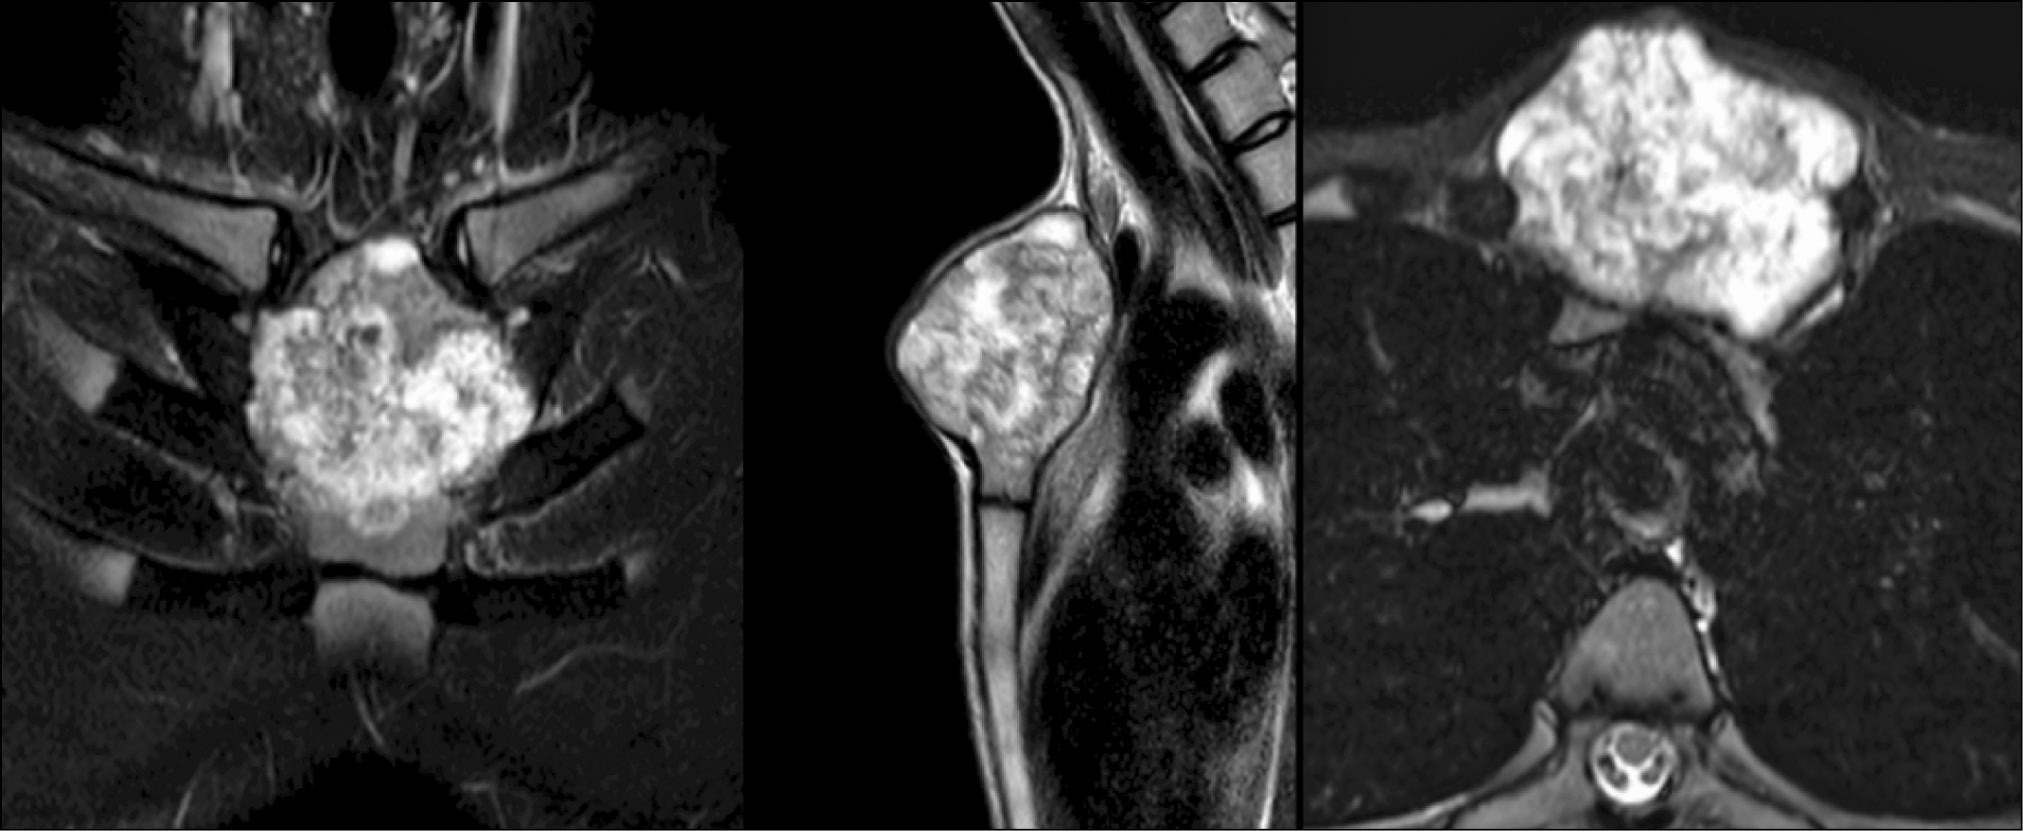

Проведена открытая биопсия патологического очага. По данным гистологического заключения поставлен диагноз: «Хондросаркома G1 рукоятки грудины». При обследовании по итогам компьютерной (КТ) и магнитно-резонансной томографии (МРТ) обнаружено объёмное образование в проекции рукоятки грудины с элементами литической деструкции костных структур (рис. 1, 2).

Рис. 1. Компьютерная томограмма рукоятки грудины пациента Г.

Рис. 2. Магнитно-резонансная томограмма рукоятки грудины пациента Г.